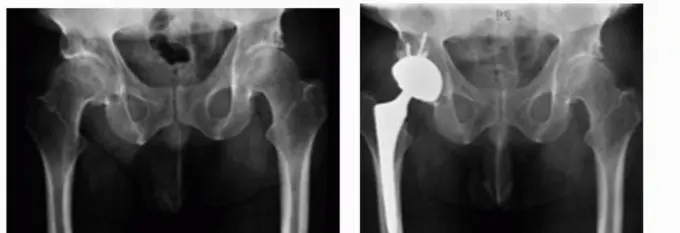

- الأشعة السينية (X-rays): هي الفحص الأول والأكثر شيوعاً. تُظهر الأشعة السينية بوضوح تآكل الغضروف (يظهر كفقدان للمسافة بين العظام)، التشوهات العظمية، النتوءات العظمية (Osteophytes)، والتكلسات. كما تُساعد في تحديد مدى النخر اللاوعائي أو كسور الورك.